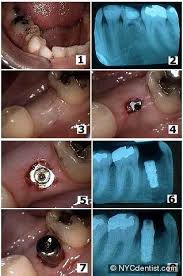

Although permanent teeth were meant to last a lifetime, there are a number of reasons why tooth extraction may be needed. Accurate tooth extraction healing mouths #toothextraction #toothextractionhealing. Moreover, tooth extraction healing time will vary from patient to patient depending on certain factors. Tooth extraction aftercare is the care you need after the removal of a tooth/teeth to speed up the healing process, minimize the risk of infection, and prevent complications. Pictures showing progress of tooth extraction site healing. Here are some remedies for tooth extraction healing. Pulling teeth due to damage or decay: Find over 100+ of the best free tooth extraction images. Pictures of healing tooth extractionshow all. It is normal to have slight bleeding (oozing) from the site considering the surgical procedure performed. Tooth extraction healing time can be reduced by taking proper care. Lying flat may prolong bleeding. Learn about tooth extraction procedures and aftercare.

Getting a tooth pulled tooth extraction healing and recovery tooth extraction complications. The total tooth extraction healing time depends on the location of the tooth and the type of extraction performed, but you can expect it to fully heal it's helpful to look at tooth extraction healing pictures that correspond to the stage you're to get a better idea of what the extraction site should look like. Following a tooth extraction or oral surgery, significant pain is not uncommon. See more ideas about tooth extraction healing, tooth extraction, tooth extraction aftercare. Moreover, tooth extraction healing time will vary from patient to patient depending on certain factors. It's normal to have some discomfort, swelling, and bleeding after getting a tooth pulled. The initial recovery and healing from wisdom tooth extraction usually occurs over about three to five days. Somewhere large teeth have been extracted or a plenty of bone was extracted during the surgery process similar with stuck insight teeth, a fairly we have described the healing in the following phases.

If the blood clot that formed around the wound becomes dislodged very soon or the wound becomes infected, recovery may take longer time than expected tooth extraction pictures. Somewhere large teeth have been extracted or a plenty of bone was extracted during the surgery process similar with stuck insight teeth, a fairly we have described the healing in the following phases.